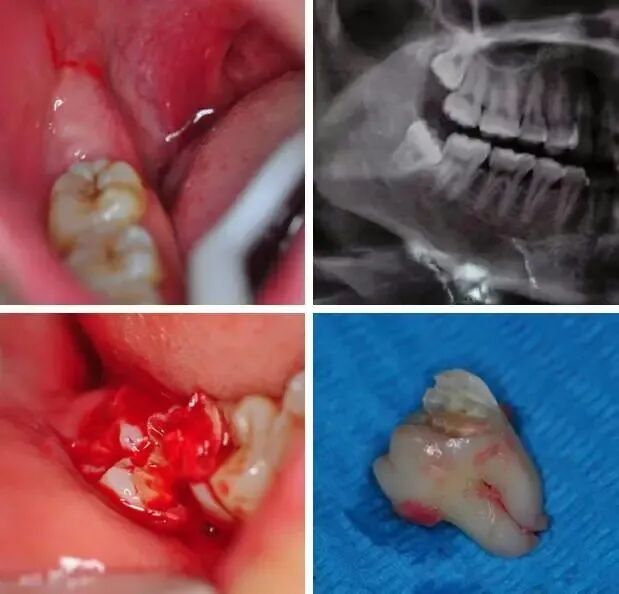

如图2(共8张图片):这个是个典型低位水平位双根智齿,也是典型运用了我的微创统筹技巧,术中出血极少,不用强吸。

如图4:两个根看着挺大,但是智齿有龋坏是死髓牙,牙周膜增宽。最终没有分根。不过还是洞穿了髓室底,目的就是为了先照着复杂准备,即使拔不下来,再分根也很快速。